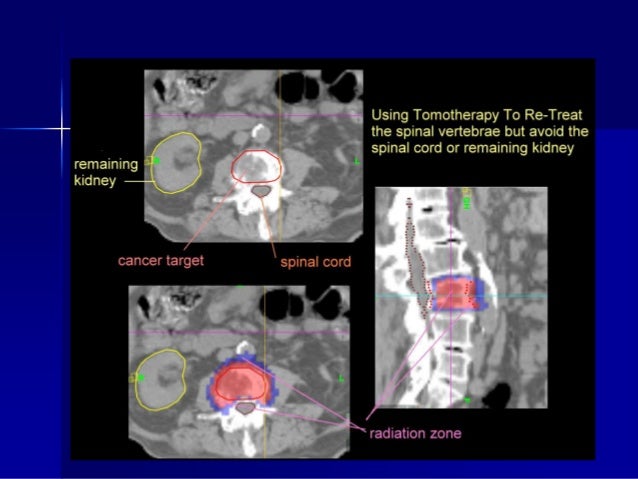

23. 23. SYSTEMATIC REVIEW

24. 24. Single fraction v multifraction more convenient less costly shorter time with acute side effects fear of high doses per fraction higher retreatment rate( 2-2,5 times higher) concern about toxicity in long-term survivors flare of bone pain maybe be higher